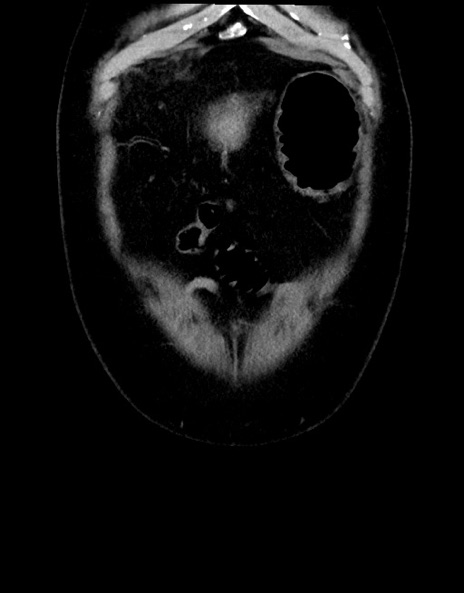

症例15(冠状断像)

横断像